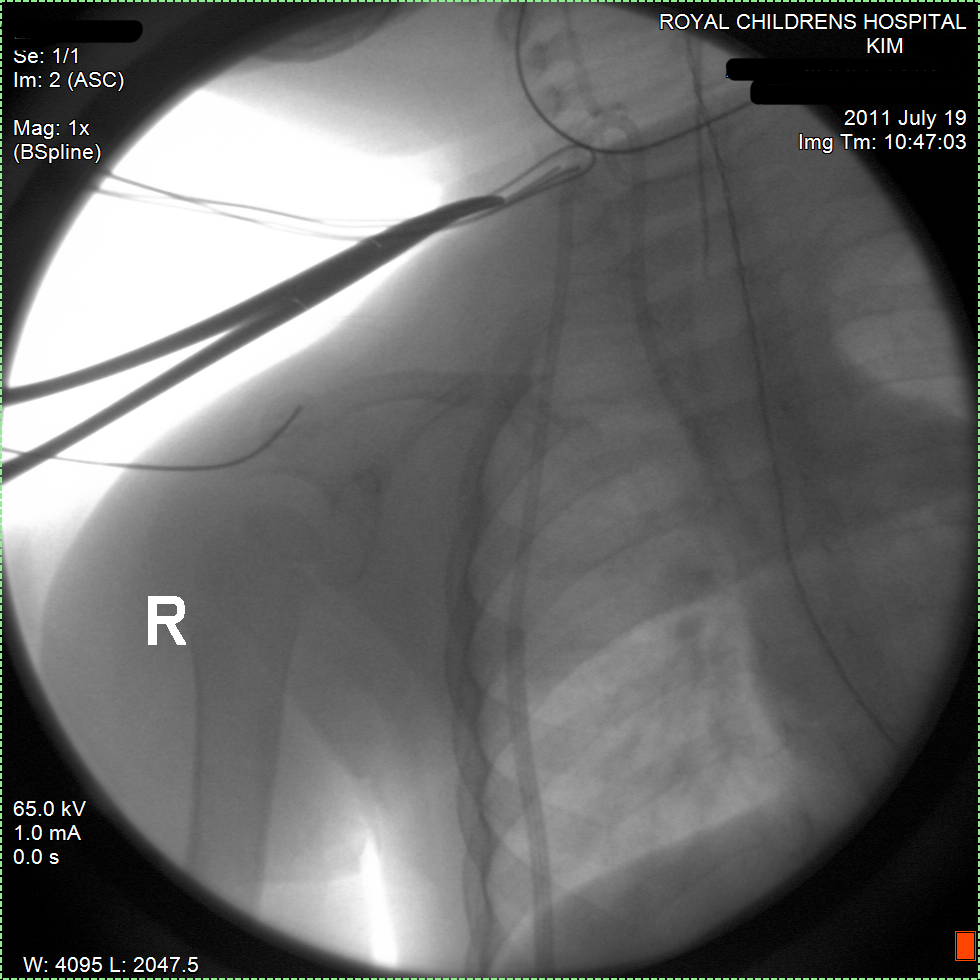

30 September 2011, Friday

07:00, met with oncology surgeon who confirmed that surgery is set for 21 October 2011. He explained that he did not expect any complications and that he is very happy with Kim's progress. He drew the picture above to explain that the Neuroblastoma node is very small and may be gone at the time of surgery, although he will still investigate the area during surgery. He also explained that he did not expect that Kim will loose her kidney. The tumour is close but did not seem to invade the kidney so she probably will not loose any part of it. While previously the tumour seemed to get too close to the arteries, now it looks very good and it will be a straight forward procedure for the surgeon. The procedure will take around 4 hours. She is planned to stay in hospital for post surgery recovery for 4 days and will probably be down and in bed for the first two. The last two days she is expected to become her active self again. Then off to home and following with next Chemos etc. The surgery date will only change if her blood levels are not good because of the prior chemo and any side effects. But it is expected she will be OK. She has been doing good so far.